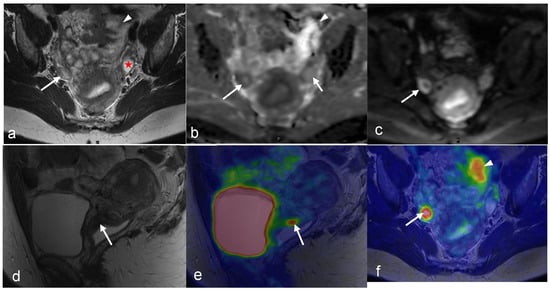

3.2. Endometrial Cancer